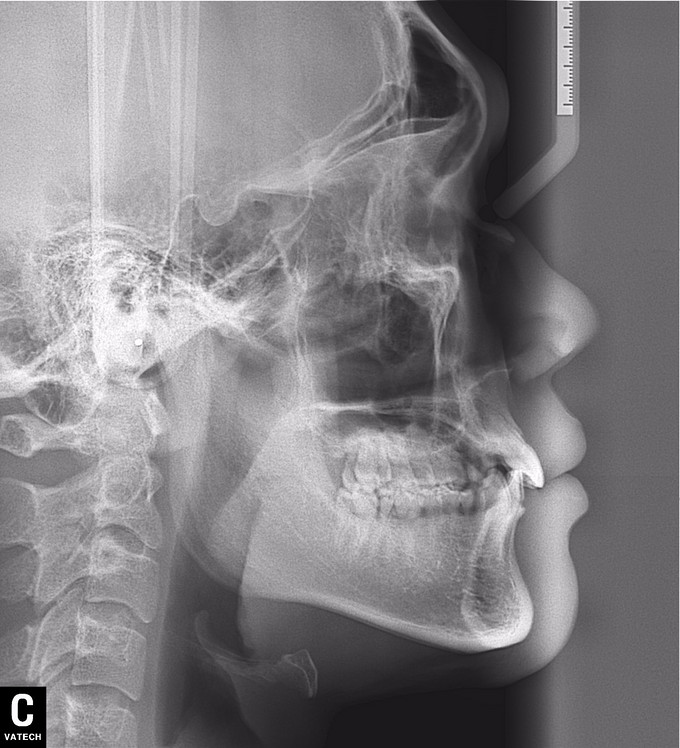

男 年龄16岁 右上恒牙2、3、4、5缺失,乳牙2、3、4、5滞留。 右下恒牙5缺失,乳牙5滞留。 左上恒牙2、3、4、5缺失,乳牙2、3、5滞留。 左下恒牙2、4、5缺失,乳牙2、5滞留。 诊断:恒牙先天缺失 治疗计划:a.乳牙治疗 b.唇系带手术 c.正畸治疗 d.种植体修复 现已经a、b两项治疗完成;因正畸难度较大,需要专家会诊共同完成!正畸治疗后再行种植修复。